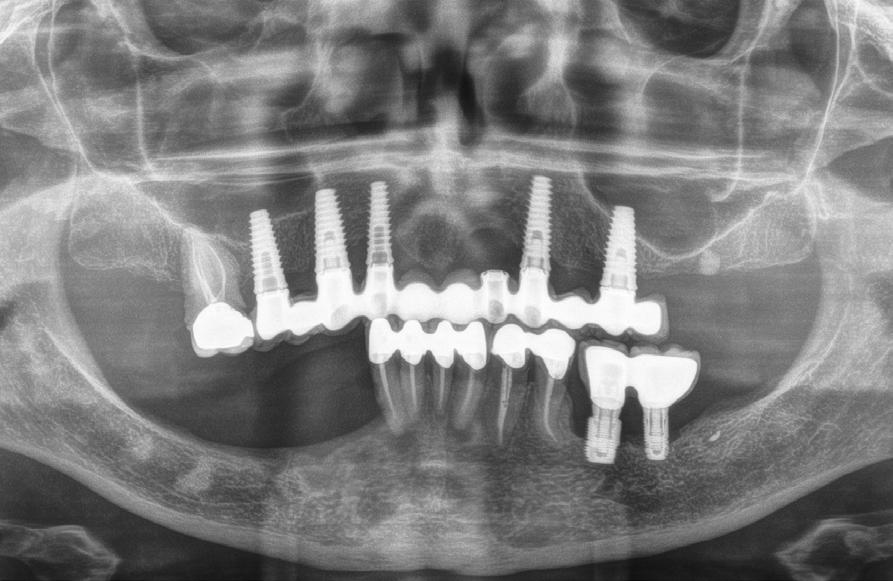

Figura 1. Radiografía inicial del caso donde observamos varios implantes con periimplantitis en el arco superior e inferior en diferentes estadios, incluso un implante que ya se ha perdido en la zona del incisivo lateral superior izquierdo y en el cuarto cuadrante.